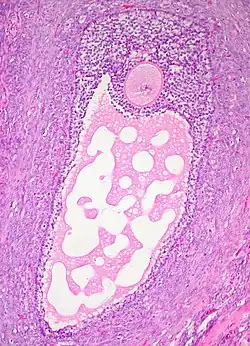

![]() Corte histológico de un folículo ovárico maduro. El ovocito es la célula grande, redonda, de tinción rosada en el centro superior de la imagen. | ||